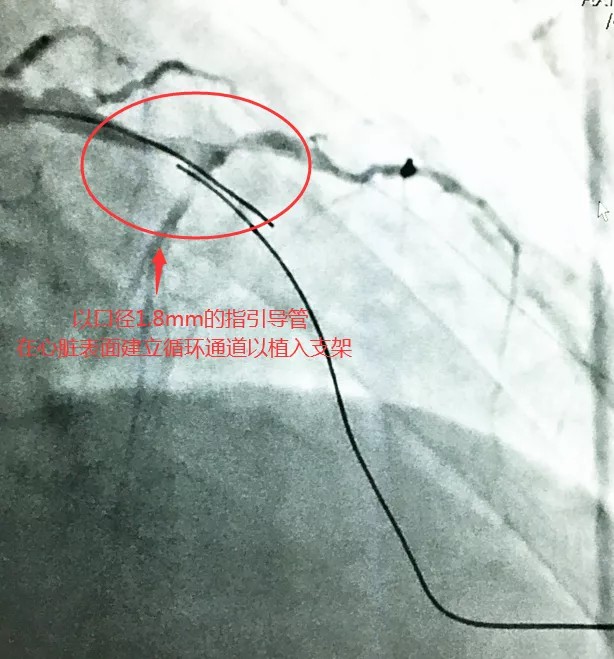

经研讨,心血管内科团队一致认为梁先生前降支闭塞后形成侧支循环,有开通闭塞前降支的适应症,但用传统的前向导丝方法治疗成功率很低,且其病变复杂、基础病多,稍有不慎会有生命危险。经研究,心血管内科团队决定打破常规,采用同侧逆向导丝方法,由于操作导丝需谨慎不可破损心脏血管,这种治疗方案对主刀医生的综合要求很高。

(导丝在心脏表面绕圈后出体外以建立通道、植入支架)